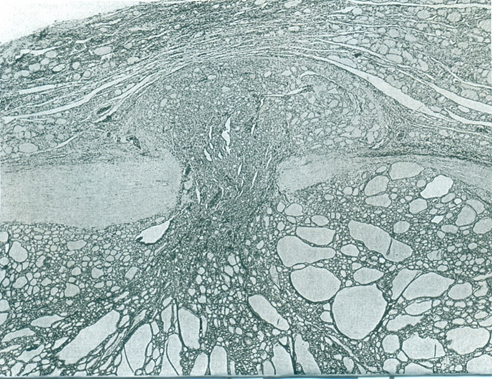

Follicular carcinoma type.- This type was the first that call our attention because of the similarity of a section we had with the case illustrated in Ackerman´s Surgical Pathology 8th edition. Page 526published byRosai; ifwe compare the figures you can see in both of them the capsular infiltration by the tumor (Figures 3A&3B). In folliculartype,atypical nuclei with frequent mitosis are seen, and the follicles are closely together without presence of fibrovascular tissue among them (Figure 4). Hürthle cells lesion. We are not considering this lesion as a malignant tumor because we have not find the nuclear changes in this condition. But is evident that they are Hürthle cells with their typical cytoplasm filled with fine acidophilic granules due to an increased number of mitochondrias (Figure 5). We shall not comment the problem of Hürthle cell neoplasias, we mention it because in one of our cases there is an area that clearly presents glandular tissue with Hürthle cell epithelia and this fact has not been previously illustrated in the newborn.

Figure 3 This picture shows follicles with atypical epithelia and frequent mitosis. There is almost no fibro vascular stroma between the follicles.

Figure 4A In Ackerman´s Surgical Pathology by Rosaipresents the capacity of tumoralinfiltration of the capsule of a follicular carcinoma.

Figure 4B Similar characteristic is find in one of our cases.